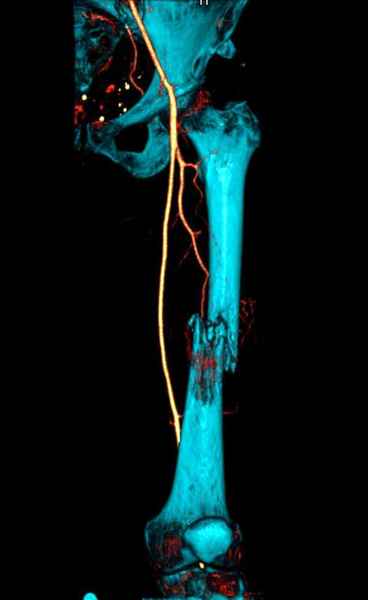

Для предупреждения кровотечения во время рассверливания, за день до операции провели эмболизацию сосудов питающий метастаз. http://radiology.rsnajnls.org/cgi/reprint/150/3/673.pdf (7-11, 12-15-16)